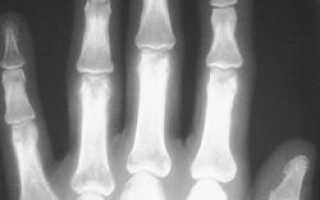

Как ни странно, но на основании обычного осмотра достаточно сложно установить обычный перелом фаланги пальца без смещения даже весьма опытному хирургу. Дело в том, что все описанные выше симптомы могут возникнуть и при сильном ушибе и при вывихе одного из межфаланговых суставов. Единственным способом на 100% разобраться в ситуации и поставить верный диагноз является проведение рентгенологического исследования.